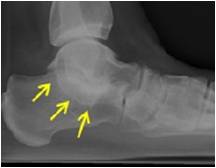

放射学特征:跟距联合在侧位X线片上呈现C sign,跟舟联合在侧位X线片上呈现食蚁兽鼻征 拍摄45°内斜位X片观察跟舟联合。跟骨轴位(Harris and beath): 跟骨轴位X线片观察跟距联合。